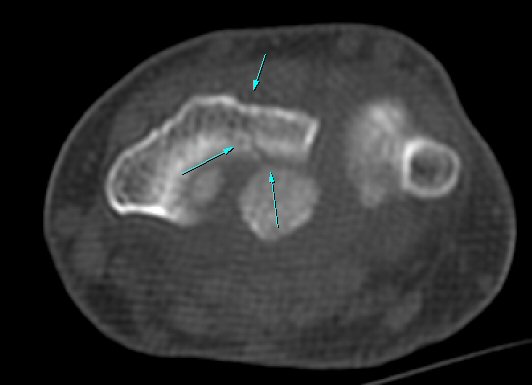

ŽÃÍÀÚ¸¦ ¾à°£ ôÃ÷À¸·Î À̵¿ÇÏ´Ï ¿ä°ñ ¸»´Ü¿¡ ÇÇÁú°ñ ¿¬°á¼º ¼Ò½Ç(loss of cotical continuity)ÀÌ °üÂûµÊ(»çÁø 2, 3).

¿ä°ñ Ⱦ´Ü¸é°Ë»ç¿¡¼­ lister's tubercle ̫̿¿¡¼­ ÇÇÁú°ñ ¿¬°á¼º ¼Ò½Ç(loss of cotical continuity)ÀÌ °üÂûµÊ(»çÁø 4).